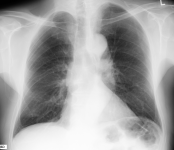

原始图像